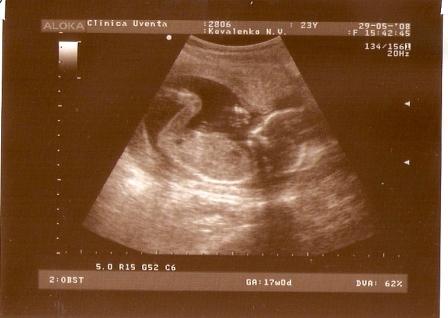

PRIKOLISTKA Опубликовано: 7 августа, 2009 Автор Жалоба Share Опубликовано: 7 августа, 2009 10- я неделя 11 - я 12- я 17-я 22- я 27-я Цитата Ссылка на комментарий Поделиться на других сайтах More sharing options...